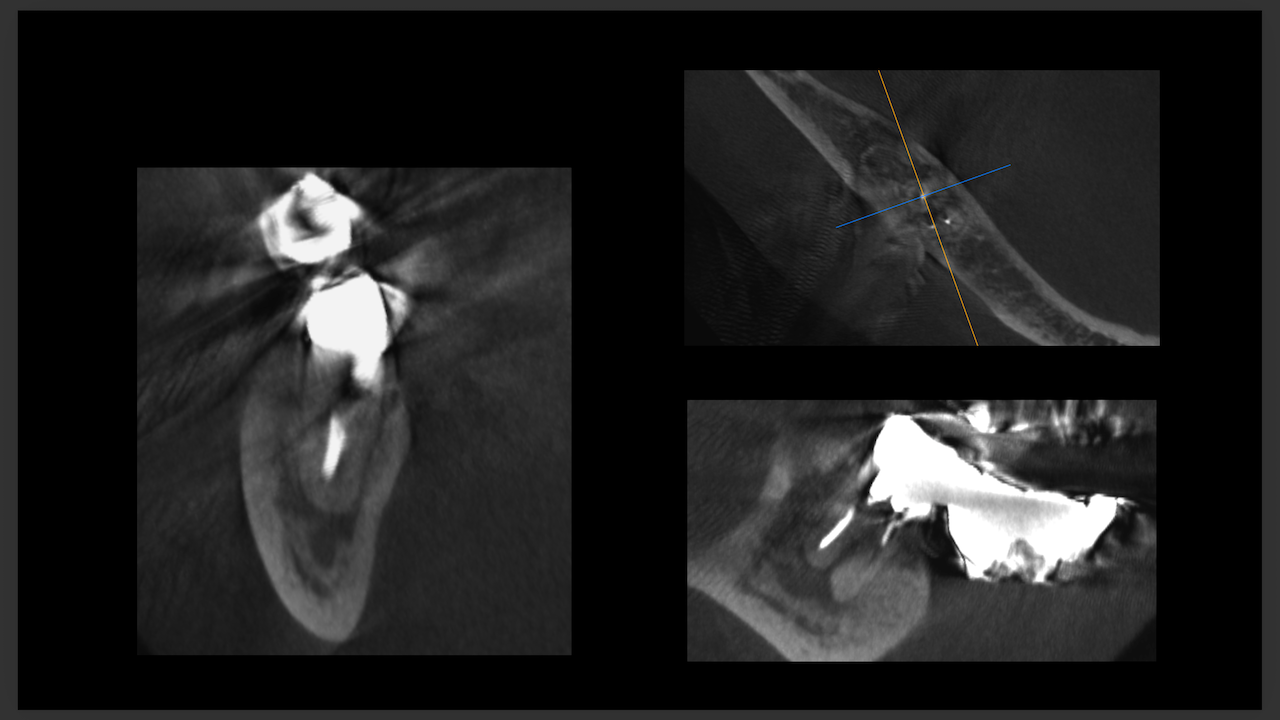

もう1ケースが以下だ。

#7がCold testに無反応である。

故に、#7,8の非外科的根管治療を行うことになった。

が、#8のメタルコアは外しにくいだろう。

CBCTでは2本とも口蓋側の皮質骨が消失している。

という絶望的な状況である。

が、

術前にその予後を患者さんに説明し、

治療へ移行した。

その結果、

ここから4ヶ月が経過すると…

臨床症状も皮質骨も大きく治癒している。

1年後の予後が気になるところであるが、すごくよくマネージメントできているだろう。